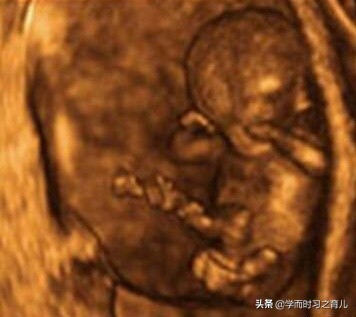

一般做四维彩超胎儿总是不露脸可能是由于宝宝正在揉眼睛、或者习惯性用手捂脸、再或者就是胎宝宝的体位挡住了脸等等。

如果做四维彩超一直看不到宝宝的脸就无法排除胎儿面部的畸形(比如唇裂等等),当然了,大部分胎儿的面部很少存在畸形情况,有时为了使孕妈咪更放心,也为了使检查更全面,医生一般会确保看到胎儿的脸,才算产检结束。

终于在第三次检查过后,表妹开心得出来了,对我说顺利过关。之后我问表妹医生怎么说的,表妹说:“医生说让我不要太担心,做四维彩超经常会遇到这种情况,一般多检查几次就可以看到胎宝宝的脸了,当然,这并不代表胎宝宝的发育出现了问题,另外,之所以一定要看到胎宝宝的脸,除了排畸,也有拍照的原因,这样可以让孕妇和家人看看胎宝宝的样子。”